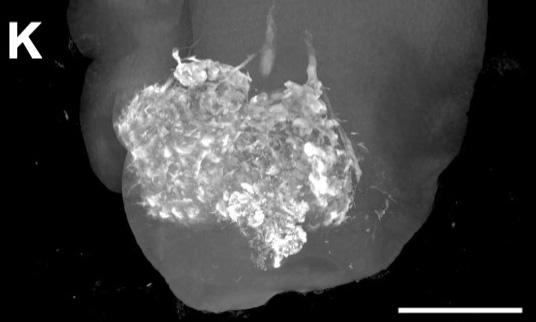

A liquid formulation can kill swathes of liver cancer cells and potentiate chemotherapy treatments, according to a study conducted in mice, rabbits, pigs and human tumor samples. The liquid could offer clinicians a safer and cheaper "bridge" to keep tumors in check in patients waiting for life-saving liver transplants. Chemotherapy remains the treatment of choice for patients with hepatocellular carcinoma (HCC), but these drugs have not made a major impact on five-year patient survival rates, which remain dismally low at around 9%. However, research has shown that liver transplantation can drastically improve outcomes in patients, raising 5-year survival rates to approximately 80%. Securing a liver transplant is therefore a major priority for clinicians and patients with early-stage disease, but organs are often difficult to find. In the meantime, clinicians keep tumors in check with local techniques such as thermal ablation - a procedure that vaporizes cancer cells with heat - but these approaches are resource-intensive, cannot be applied to all tumors, and can damage surrounding tissues. Hassan Albadawi and colleagues designed an alternative ablation technique based on an ionic liquid named LATTE, which can deliver both ablating agents and chemotherapy drugs directly into tumors. The team found that injections of LATTE shrank tumors either alone or in combination with the chemotherapy drug doxorubicin in rat and rabbit models of HCC, and rapidly killed cancer cells in 12 resected human tumors. "We anticipate that the safety profile of LATTE, its low cost, its simplicity of use, and the flexibility to repeat the procedure will make this [technique] appealing to physicians," the authors say.